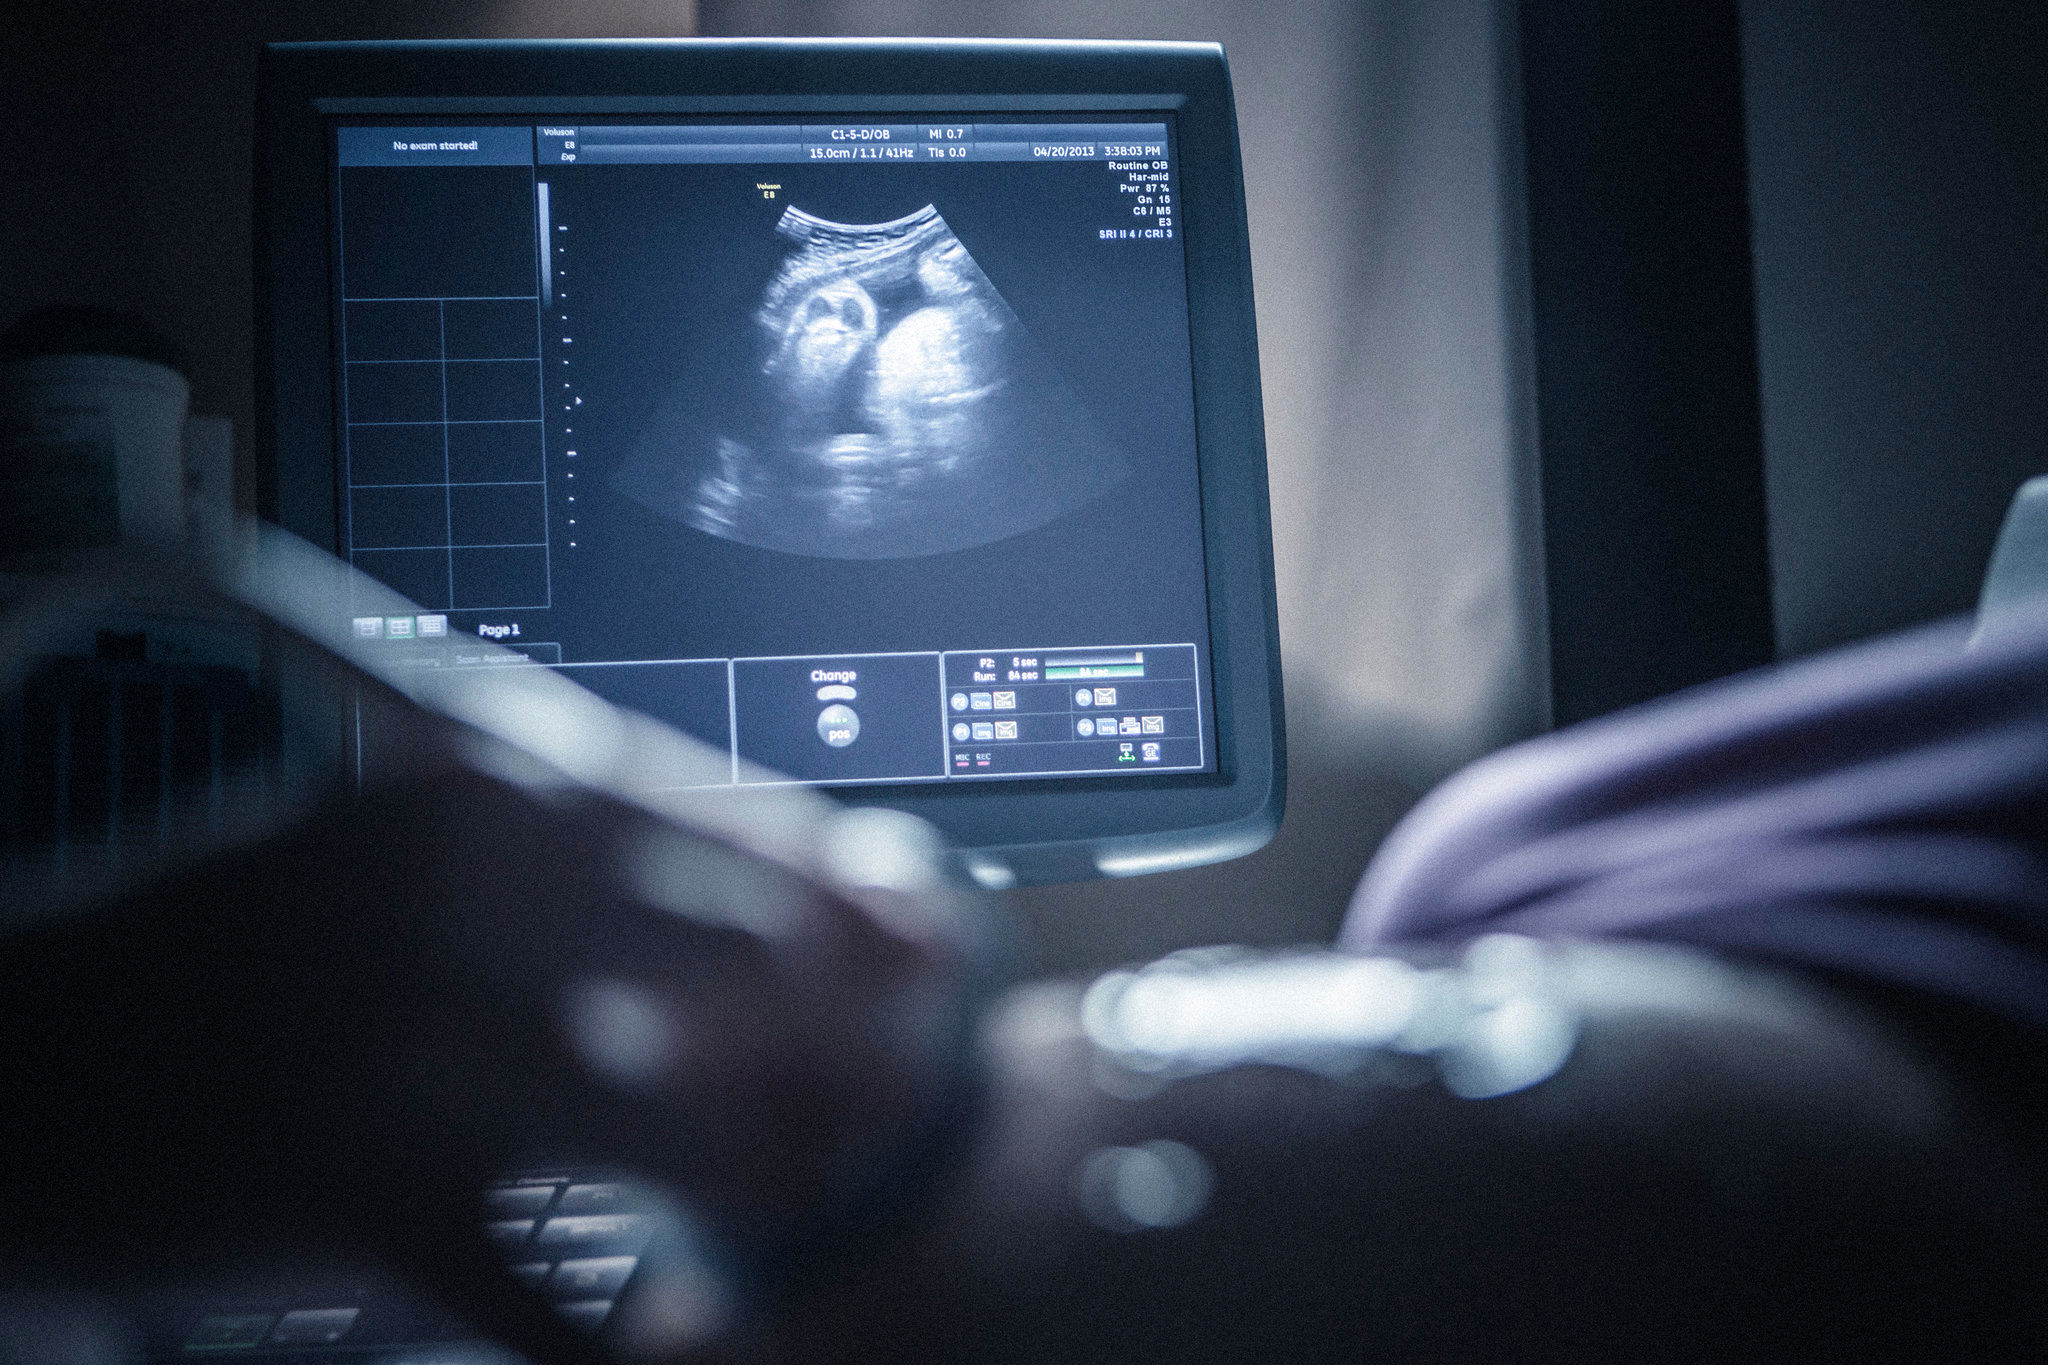

دبیر ستاد ملی جمعیت درباره برخی اظهارات مبنی بر توقف اجرای غربالگری در دوران بارداری، گفت: غربالگری در کشور ما انجام می‌شود و ممنوعیتی برای انجام آن وجود ندارد.

به گزارش ۲۴ آنلاین، مرضیه وحید دستجردی، در توضیح بیشتر این موضوع اظهار کرد: برخی تلاش داشتند با تصویب قانون، انجام غربالگری را ممنوع کنند؛ اما پیگیری‌ها و اقدامات متخصصان زنان مانع از تحقق این امر شد. در نتیجه، غربالگری همچنان به عنوان یک فرآیند رسمی در نظام سلامت کشور اجرا می‌شود و حتی جایگاه قانونی دارد. از این‌رو، هیچ ممنوعیتی در این زمینه اعمال نشده و برنامه‌های غربالگری همچنان در کشور ادامه دارد.